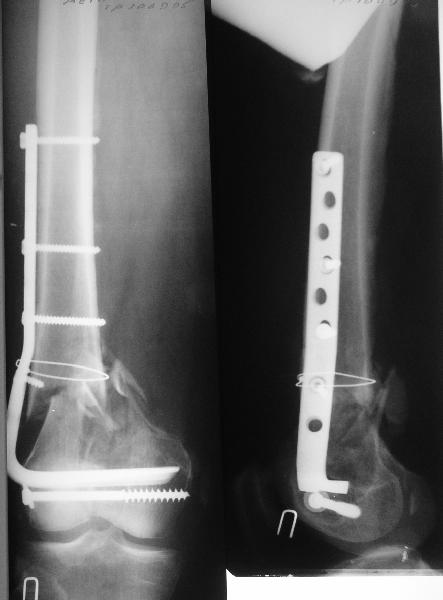

Длину восстановили, возможно, даже с изьбытком, ну да динамизируем пораньше. Введенные в овальное отверстие дистальые винты имеют угловую стабильность. Снимки приложены. Заранее спасибо за критику и комментарии.

Довольно симпатично получилось. Не сомневался, что будет именно такой антеградный реостеосинтез.

Была ли педресация на столе после окончательной фиксации? Уверен ли ты, что "угловая стабильность" дистальных винтов позволит агрессивно заниматься разработкой движений в коленном суставе?

Nicely executed surgery with good planning resulting in great looking x-rays but not the best the way to deal with this fracture. Earlier fracture was having slight translation with no angulation and no instability, now ur fracture is distracted with potential instability as your construct is not the best suited to this place, so more likelihood of non union or complications.

Good luck to you and your patient

Should have preferred a locking plate if at all u wanted to reoperate and

added copious bone graft.